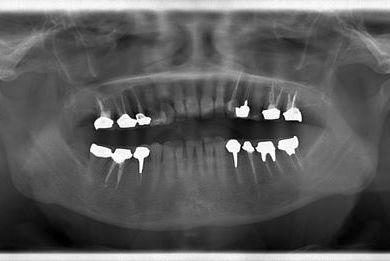

| 性別/年齢 | 女性 / 51歳 | ||||||||||||||||||||||||||||||||

| 主訴 | 前の歯の治療後の変色が気になる。詰め物がとれた箇所あり。痛みあり。 | ||||||||||||||||||||||||||||||||

| 治療方針 | セラミック治療にて、審美的回復を行う。 | ||||||||||||||||||||||||||||||||

| 治療内容 | オールセラミッククラウン7本(オールセラミック用土台1本)、ハイブリッドセラミッククラウン10本(ハイブリッドセラミック用土台9本)、ハイブリッドセラミックインレー1本 | ||||||||||||||||||||||||||||||||

| 総治療費 | 961,800円 | ||||||||||||||||||||||||||||||||

| 治療期間 | 10ヶ月 |